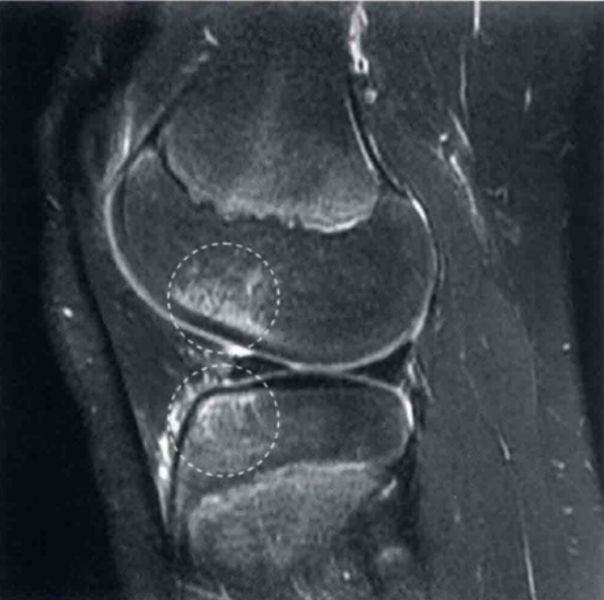

图3 a和b显示的为冠状位质子加权像和轴位T2像,并在关节镜下证明了为ACL股骨端撕裂。

在a中ACL股骨止点的信号增强,并且不能看到切带附着点(圆形区)。在b中ACL股骨附着点缺失(圆形区)。将图3b与图1b对比观察可显示正常的股骨止点